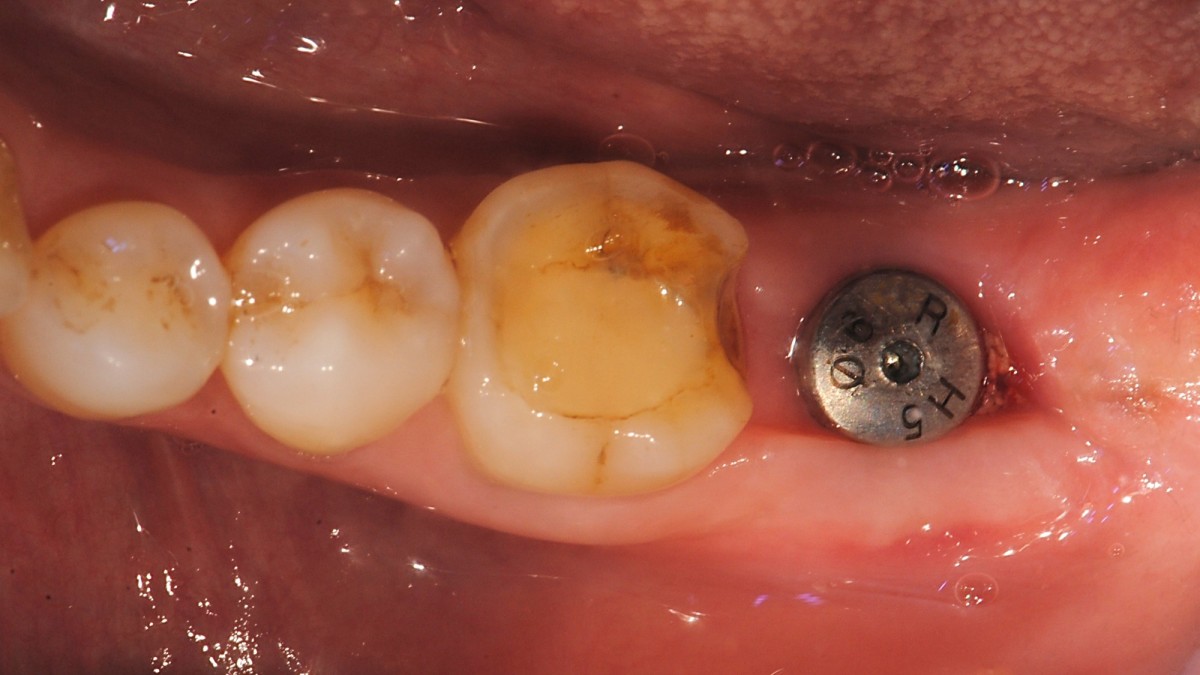

SIngle Implant - Immediate Placement, 8-year follow up

<CJ SBN> old female had mobility and pain when chewing in the lower molar